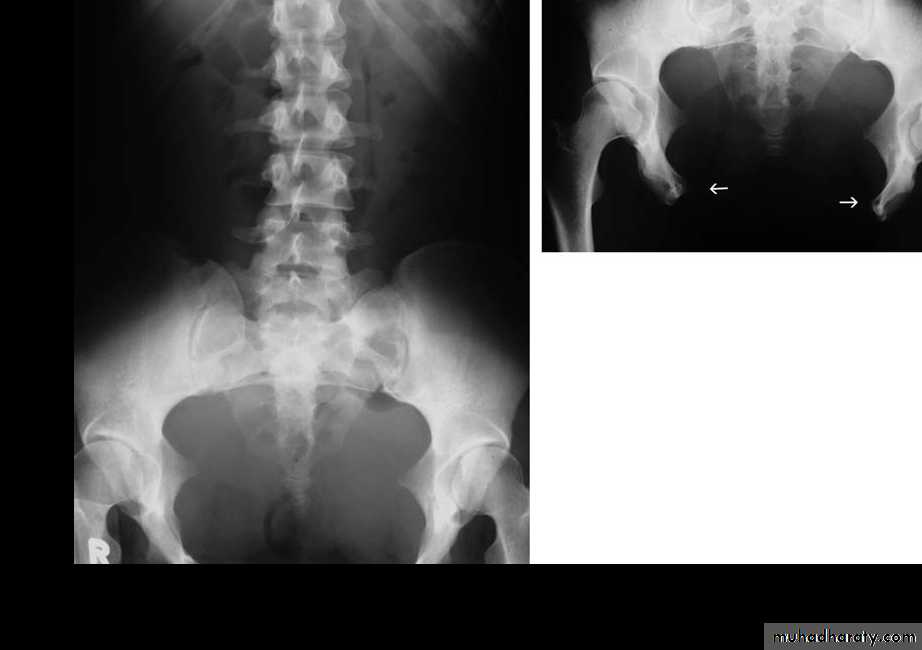

Anorectal Anomalies